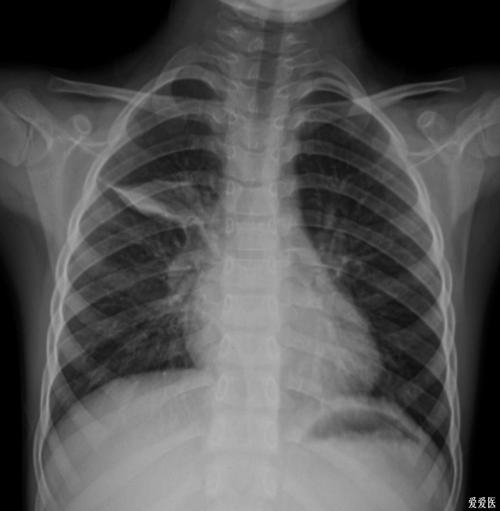

胸部正,侧位dr片——治疗前后摄片对比

胸部正位dr片双肺多发透亮影